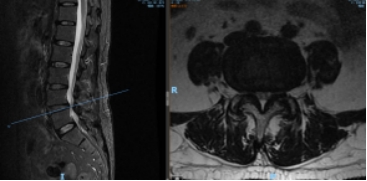

术前 MR 术后 MR